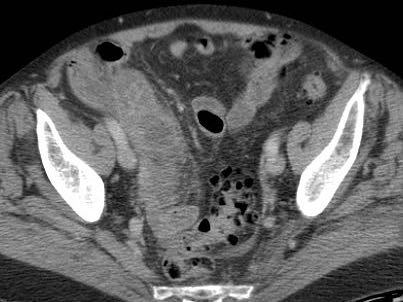

Ở bệnh nhân này, siêu âm cho thấy lượng lớn mô mỡ viêm (*) và hồi tràng dày thành, biểu hiện quá trình bao bọc thành công tình trạng thủng (sắp xảy ra) của ruột thừa (mũi tên).

Lưu ý sỏi phân vôi hóa (mũi tên trên CT) trong ruột thừa ở mức cao hơn.